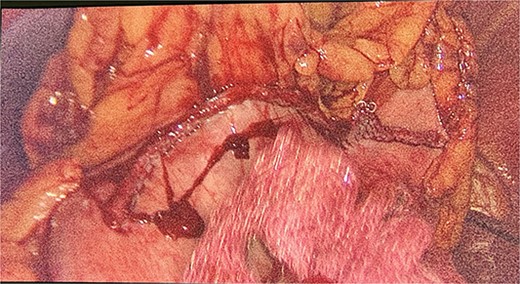

Intraoperatively, the location and resection of the left suprarenal gland (Fig. 2) was found located on the apex of left kidney underneath the body of the pancreas.

We had to first liberate the adhesions of the colon from a previous operation before gaining entry to the left colon. To do so, we made an incision in the White line of Toldt and dissected the right gastrocolic and splenocholic ligaments. This allowed us to access the retrocolic space and approach the left kidney. We identified the left renal vein and the left suprarenal gland and dissected the gland from the fatty tissue of the kidney. The gastrosplenic ligament was also liberated through the ligation of short gastric arteries. After separating the stomach from the posterior abdominal wall, we located the GIST (Fig. 3) on the posterior part of the fundus and removed it through wedge resection (Fig. 4).